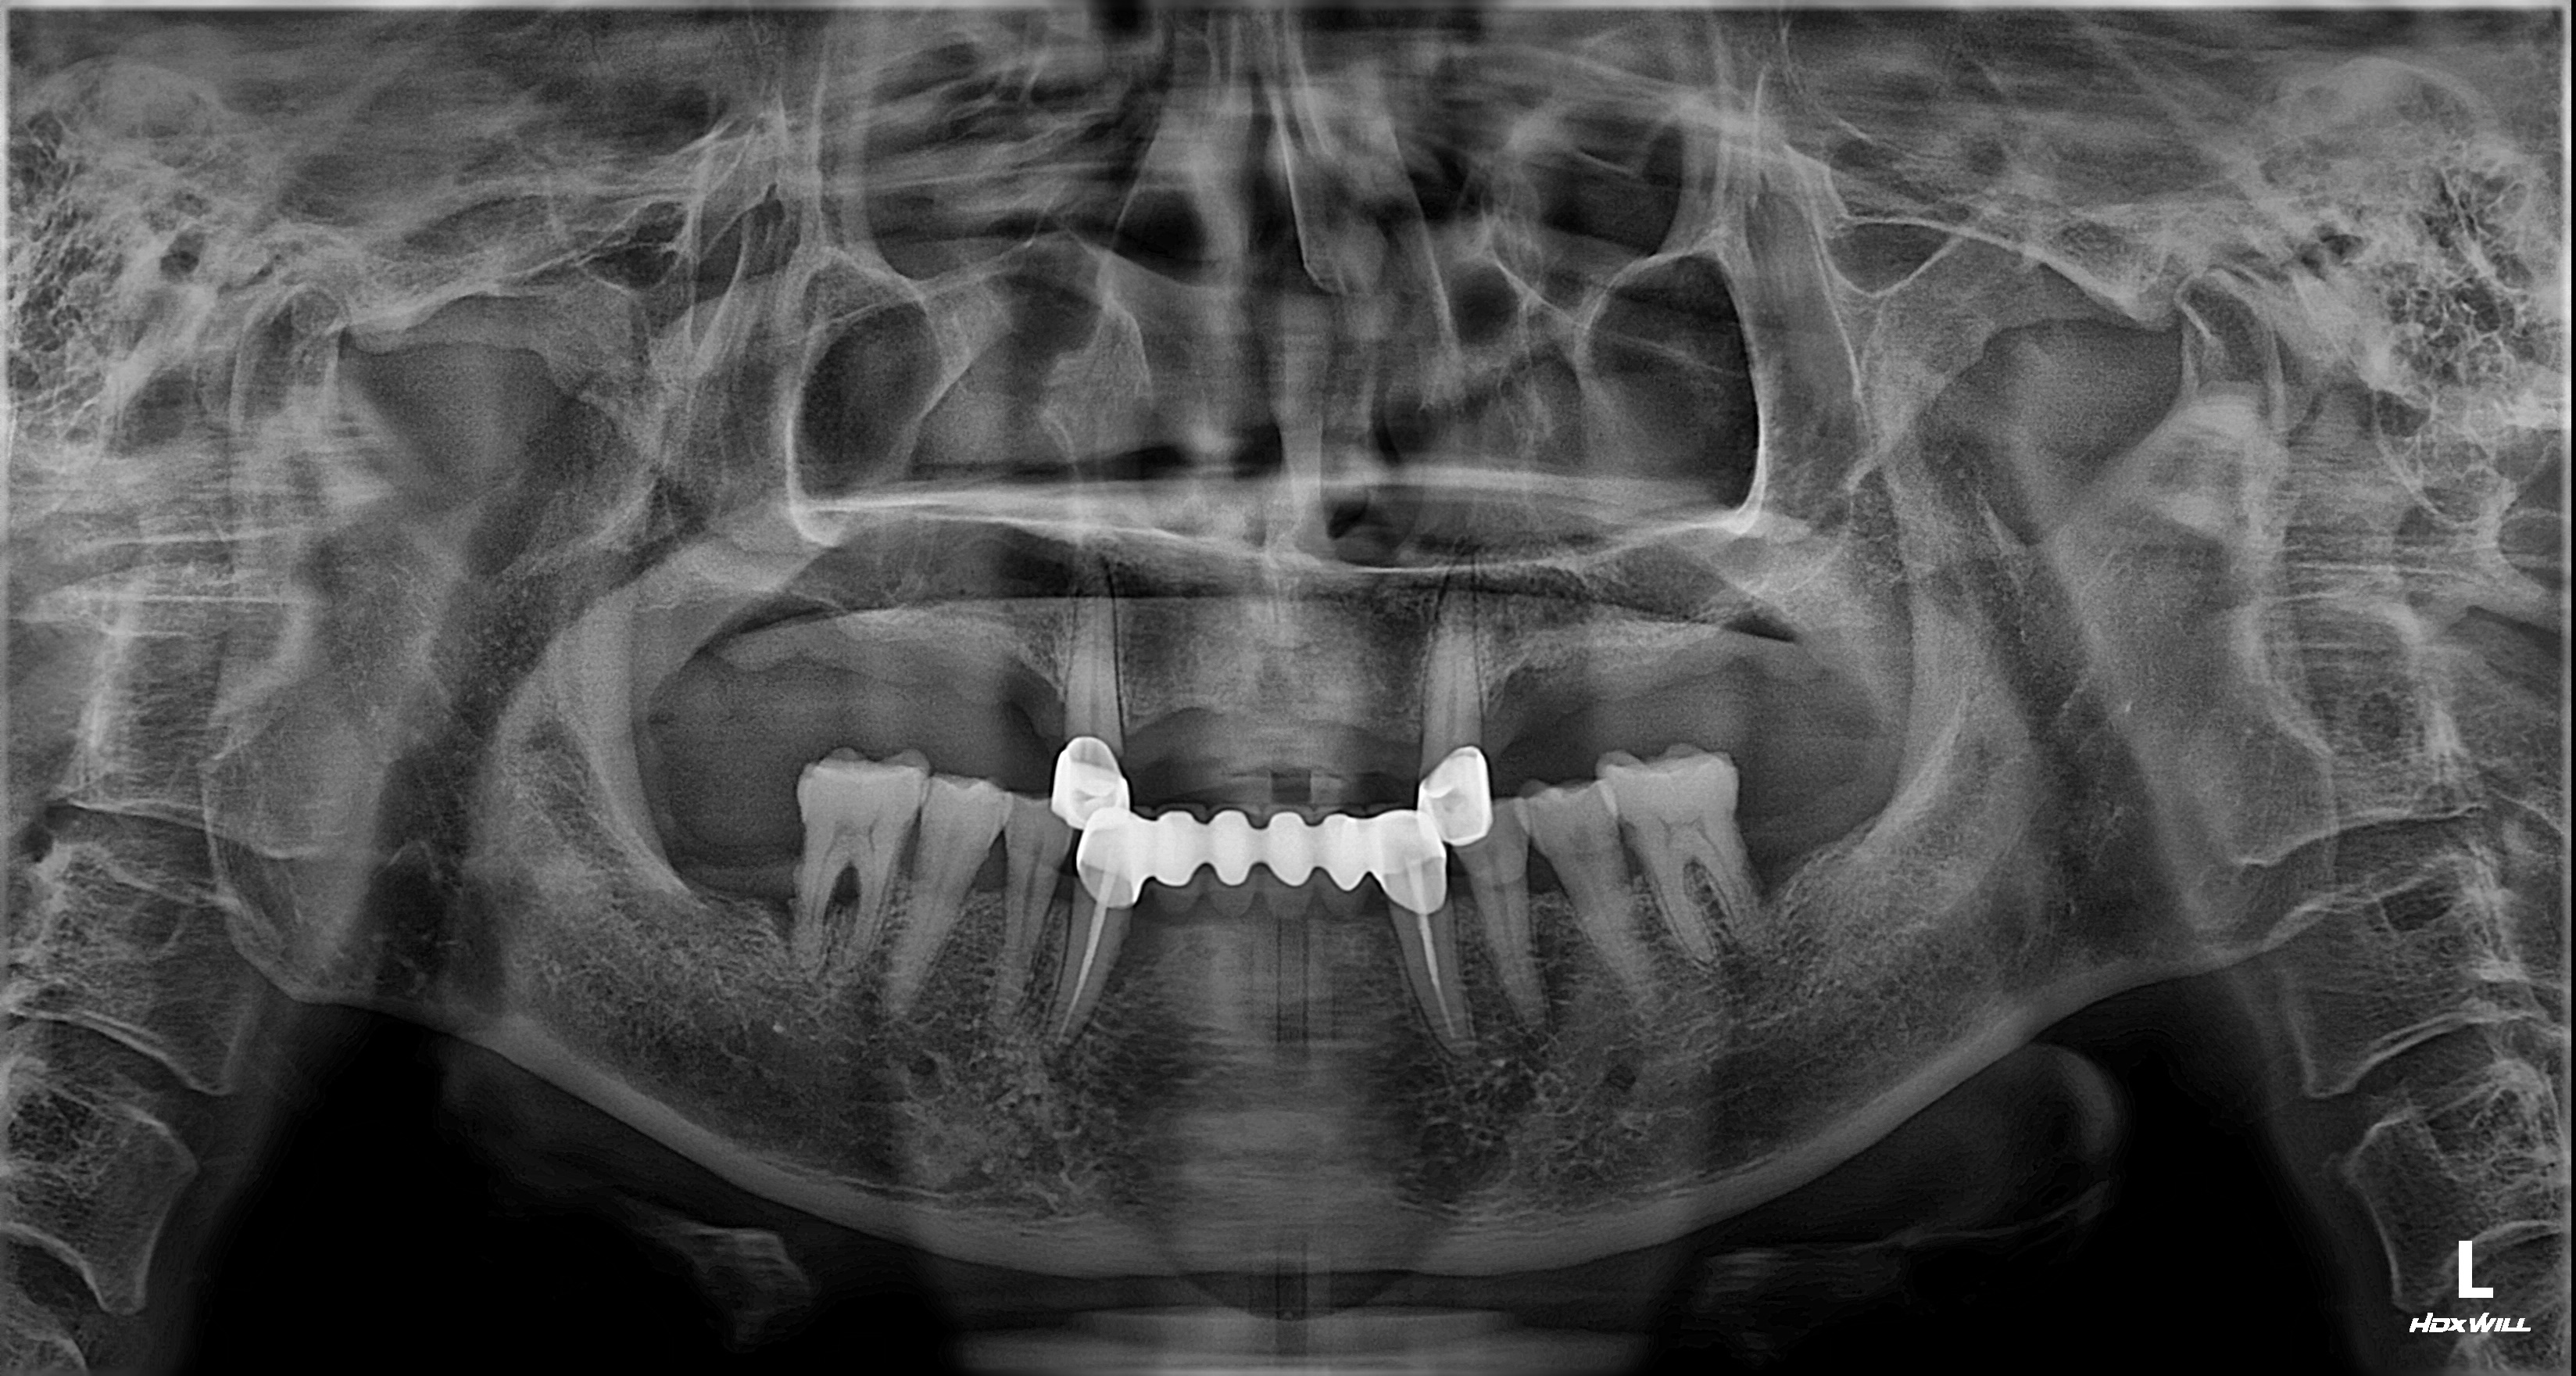

촬영일시: 2025.08.31.